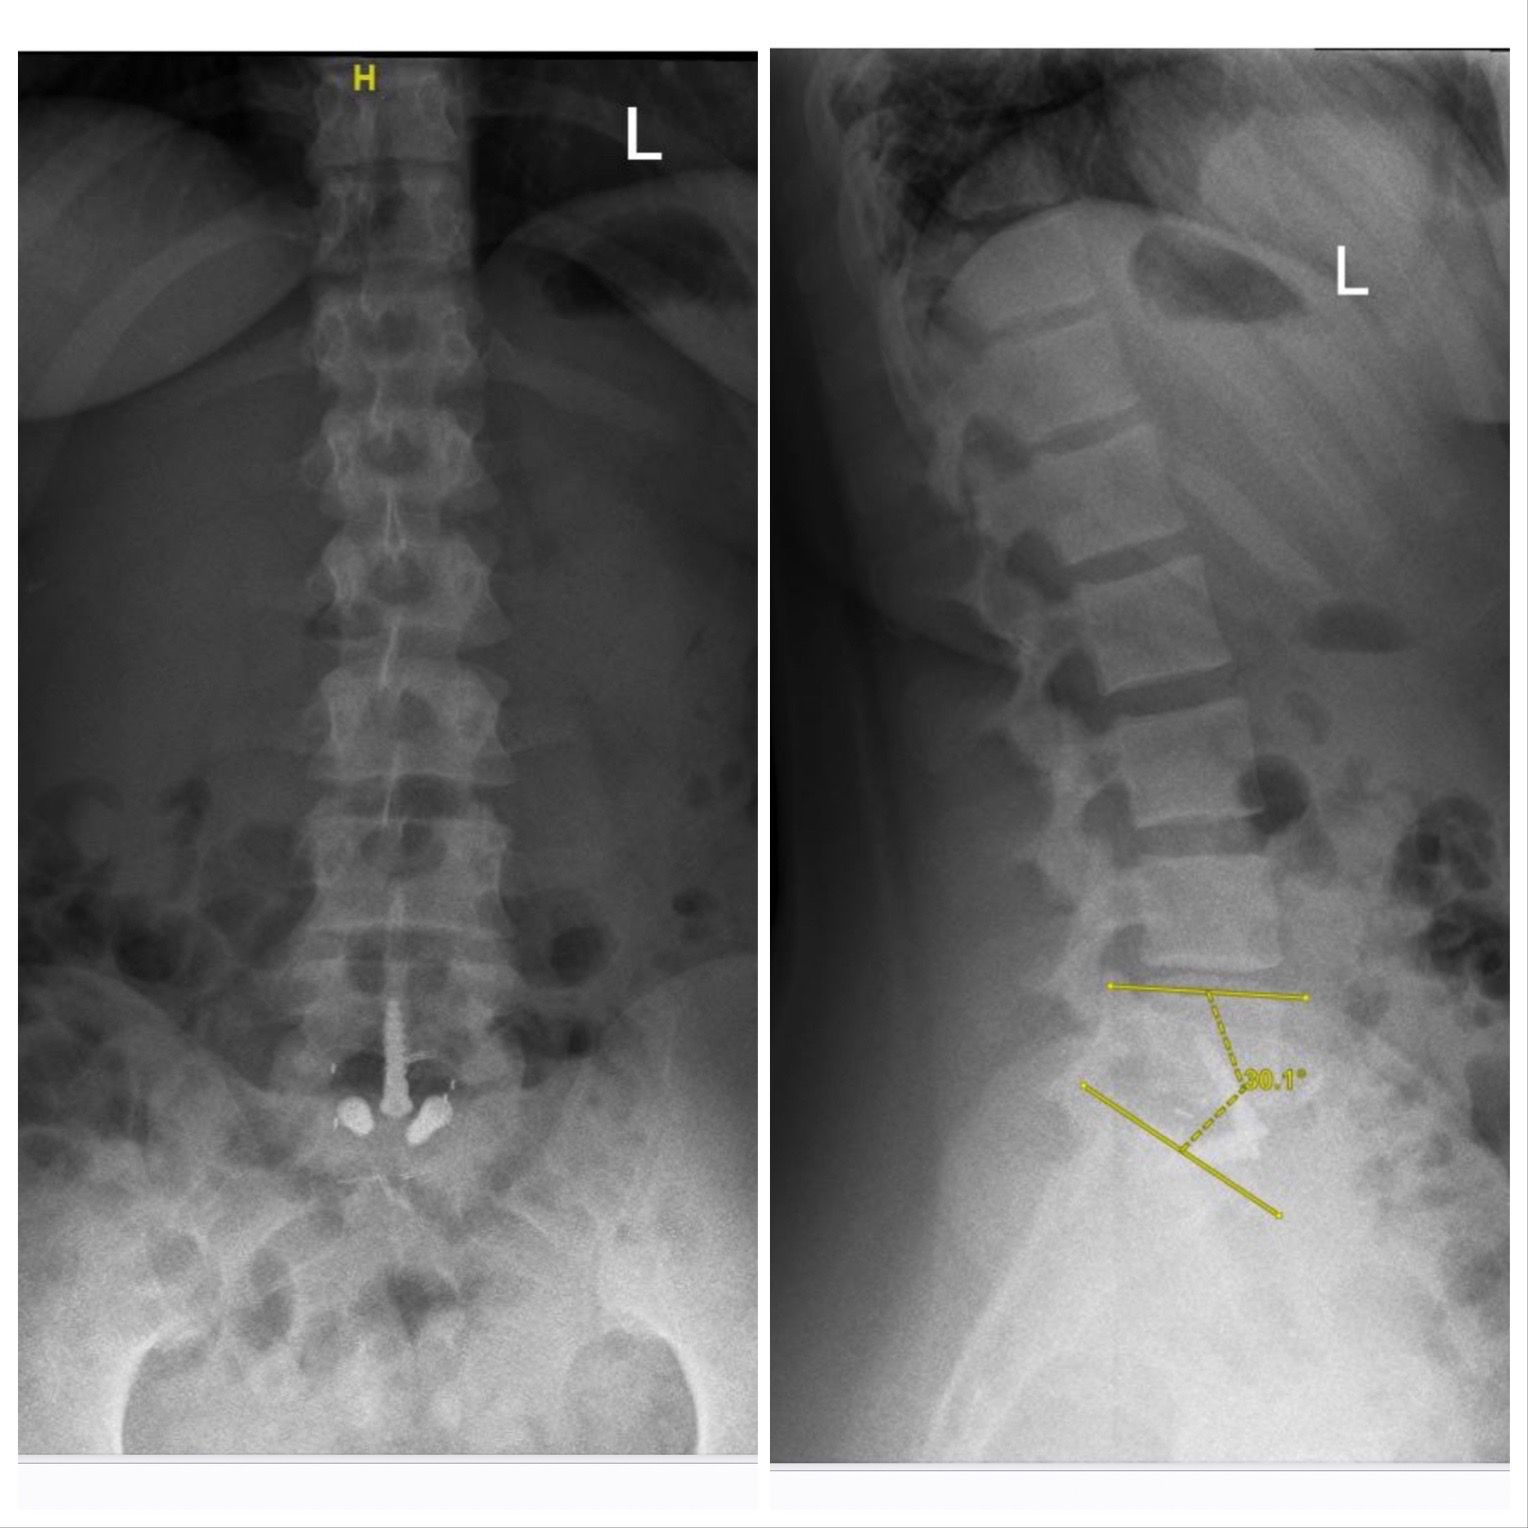

أجرى فريق طبي بقيادة أستاذ مساعد جراحة المخ والأعصاب والعمود الفقري بمستشفى الملك فهد الجامعي بالخبر التابع لجامعة الإمام عبدالرحمن بن فيصل، الدكتور سلطان السالمي، عملية تغيير لغضروف الفقرات القطنية عن طريق البطن لشابة تعاني من الآلام أسفل الظهر تبلغ من 28 عامًا.

وتابع أن هذه العملية تعد من العمليات المعقدة خاصة أن المريضة كانت تعاني من الآلام منذ خمس سنوات، وتمكنت من إجراء العملية وتماثل المريضة للشفاء وذلك بتقنية حديثة لمعالجة الآلام الظهر المزمنة وقد استغرقت مدة العملية ساعتين.